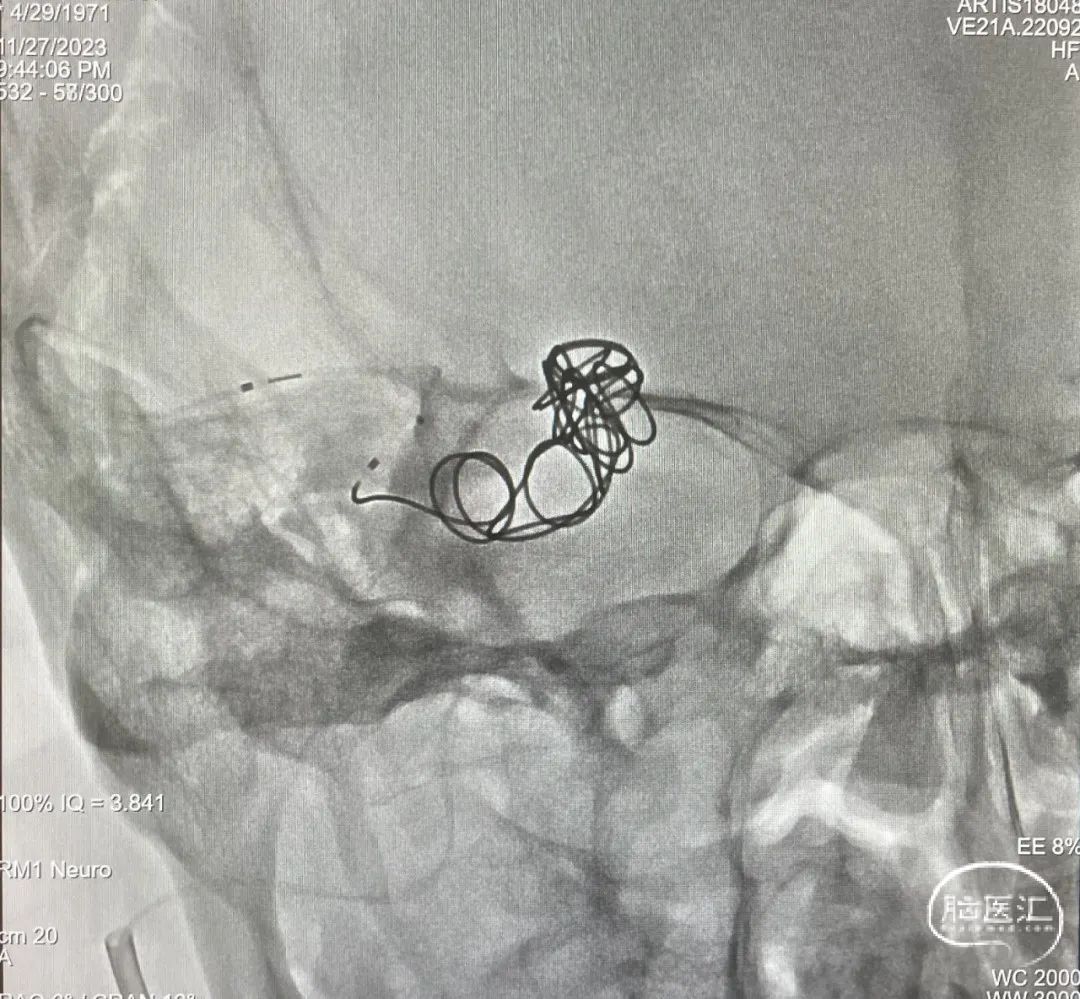

由于瘘口流量大,为了防止栓塞材料过度弥散,并逃逸至深静脉,首先通过Echelon-10微导管向静脉球内填入Feng 12/40、Feng 10/30两枚弹簧圈,限制后续液态栓塞材料仅在静脉起始部弥散。

随后回撤Echelon-10微导管,并通过Echelon-10微导管和Marathon微导管交替注入Onyx-34、Onyx-18,此时可见Onyx首先被血流冲至静脉球内,但被弹簧圈篮筐限制,并在瘘口范围内弥散。

通过“注射-停顿-再注射”,Onyx进一步在瘘口及供血动脉段和引流静脉起始部弥散满意

造影显示瘘口不显影,无静脉早显。